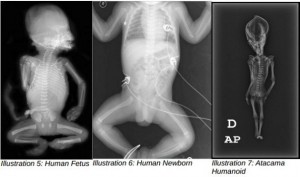

ნოლანმა და მისმა კოლეგებმა ეს უცნაური ეგზემპლარი 2012 წლის შემოდგომაზე გამოიკვლიეს მაღალი რეზოლუციის ფოტოგრაფიითა და რენტგენის სხივებით, მოახდინეს სკანირება კომპიუტერული ტომოგრაფიით და შეამოწმეს დნმ-ის ნიმუშები. მკვლევარებს სურდათ, დაედგინათ, რა იყო ანომალიური ჩონჩხის განვითარების მიზეზი, რატომ ჰქონდა ნაკლები ნეკნი, რა ასაკში მოკვდა, მუცლად მყოფი ნაყოფი იყო, დაბადებისას გარდაცვლილი თუ ბავშვი, ან სულაც სამხრეთ ამერიკის რომელიმე პრიმატი.

ანალიზმა ასევე გამოავლინა თავის ქალის დეფორმირებები და სახისა და ყბის განუვითარებლობა, აღინიშნებოდა აკროცეფალიაც, იგივე მაღალი თავის სინდრომი – თანდაყოლილი ეფექტი, რომელიც გამოიხატება თავის ქალის წაწვეტებულ ფორმაში.